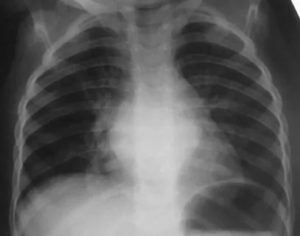

Бронхит на рентгеновском снимке

Как выглядит бронхит на снимке и как его диагностировать:

- рисунок легких изменен – мелкие сосуды незаметны;

- можно увидеть очаги спадения ткани;

- корень легкого теряет четкий контур и увеличивается;

- стенки бронхов становятся утолщенными;

- становятся заметны очаги инфильтратов;

- контур теряет свою четкость;

- могут быть заметны участки тканей без сосудов;

- в нижней части легких могут локализоваться светлые пузырьки, светлый цвет говорит о их воздушности.

Если профессиональный язык рентгенолога перевести на простой, понятный любому человеку, то по снимку можно выяснить – присутствует ли отек легкого, есть ли рубцовая ткань или деформированы ли бронхи.

Рентген не покажет сам бронхит, он отобразит диффузные изменения в тканях, позволит обнаружить изменение формы и содержимого органов дыхания. Если бронхит запущен, можно заметить признаки эмфиземы.

При бронхите на снимке отмечаются деформация (искривление) бронхов, а также разрастание соединительной ткани. При хроническом бронхите область патологических изменений больше, поэтому его лучше видно на снимке. Заметны прикорневые просветы легких, которые сверху оттеняются узкими полосками, в целом рисунок напоминает рельсы.